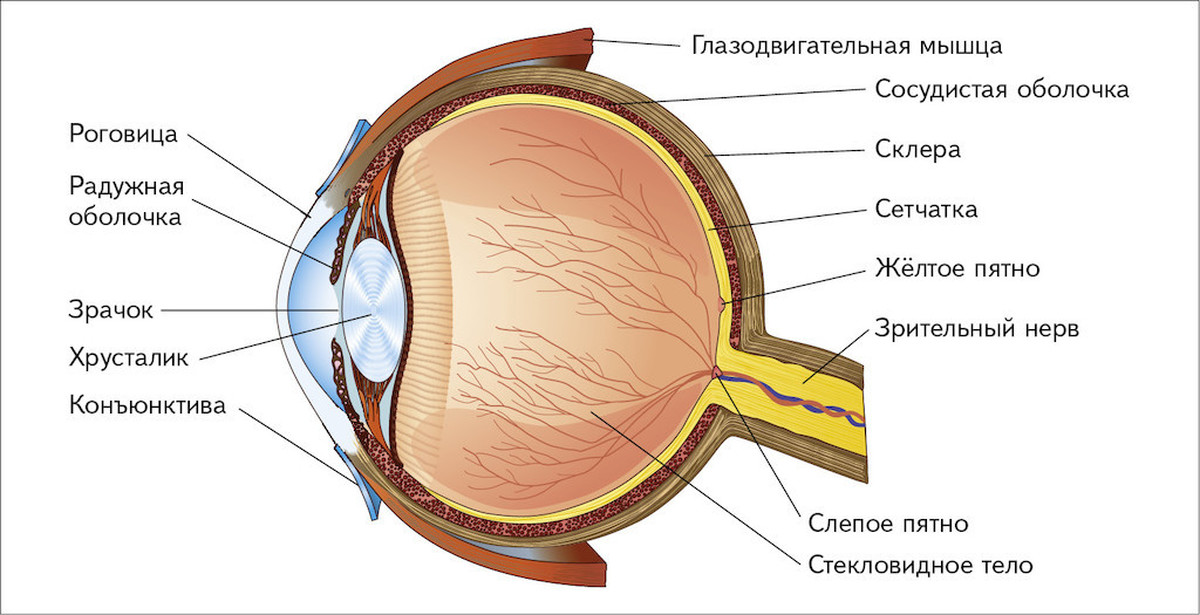

Изображения и анатомия сетчатки глаза

Раздел: Визуальный дайджест